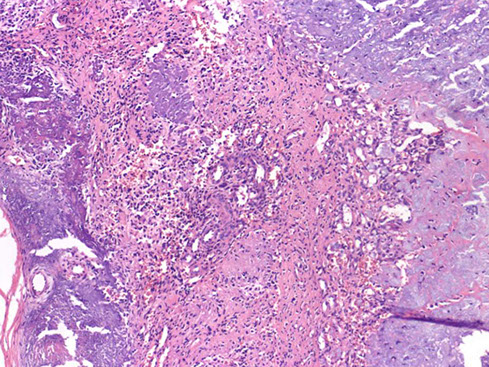

Angiomatoid Fibrous Histiocytoma (AFH)

Gross: firm, circumscribed, multinodular or multicystic hemorrhagic mass, avg 2 cm

Micro: 3 main findings: 1) irreg solid mass of histiocyte-like cells; 2) cystic areas of hemorrhage (bloody lakes), and 3) chronic inflam (cuff of lymphs)

- thick fibrous capsule around nodule/sheets/ of whorls of monomorphic bland spindle to ovoid reddish cells

- hypercellular c bland histiocytoid cells and hemorrhagic cystic spaces, with aggs of lymphoid cells at tumor's edge

AFH